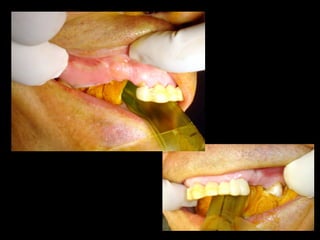

• Paciente de 25 años con

pérdida casi total de

dientes superiores y

prótesis mal adaptada.

• Ganchos que no

cumplen su función.

Modelos de estudio, a la izquierda sin la prótesis a la derecha con la prótesis, el

molar izquierdo con destrucción casi total de la corona y sin utilidad protésica.

• Paciente de25 años con pérdida casi total de dientes superiores y prótesis mal adaptada. • Ganchos que no cumplen su función.

Modelos de estudio,a la izquierda sin la prótesis a la derecha con la prótesis, el molar izquierdo con destrucción casi total de la corona y sin utilidad protésica.